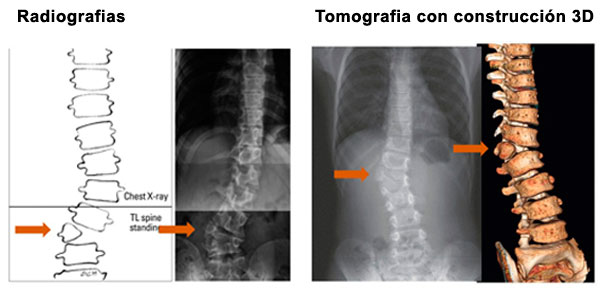

Es necesario evaluar con detalle al niño y solicitar estudios de imágenes que nos puede mostrar la estructura de la columna en forma completa.

El especialista usualmente observa si la curva está aumentando.

En algunos casos las curvas no aumentaran y en otros casos se evidenciará un aumento progresivo de la deformidad.

Se necesitará controles periódicos (4-6 meses) para comparar con estudios radiográficos si la curva está aumentando o está detenida.

Paciente de 1 año y 8 meses con escoliosis congénita progresiva, se realizó resección de hemivertebra con colocación de tornillos transpediculares